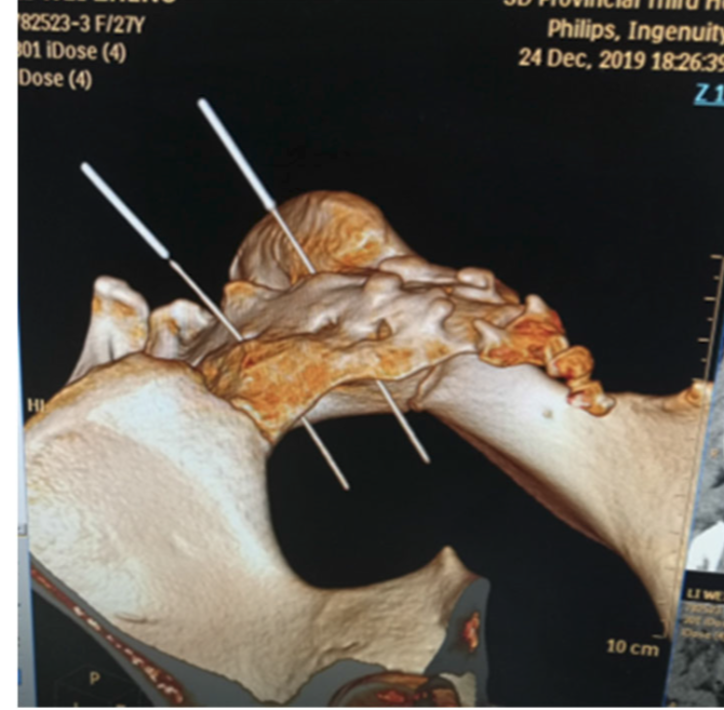

Figure 5. Angle de puncture au 32V (Bai TY et al., 2022)

Au point 32V, la puncture est orientée de manière caudale dans le plan frontal. L’angle d’insertion, défini par rapport au plan cutané, est mesuré cliniquement à l’aide d’un goniomètre. La tomodensitométrie réalisée aiguille en place, avec reconstruction tridimensionnelle, confirme la position intraforaminale de l’aiguille.

Figure 7. Profondeur de puncture (Bai TY et al., 2022)

La reconstruction tomodensitométrique tridimensionnelle, réalisée aiguille en place, permet de visualiser la position de l’aiguille depuis les tissus mous postérieurs, son trajet intraforaminal puis le dépassement du foramen sacré antérieur. Les données issues des études anatomiques et d’imagerie suggèrent que ces trois segments anatomiques sont d’un ordre de grandeur comparable, d’environ 15 à 20 mm, variable selon la morphologie du sujet.